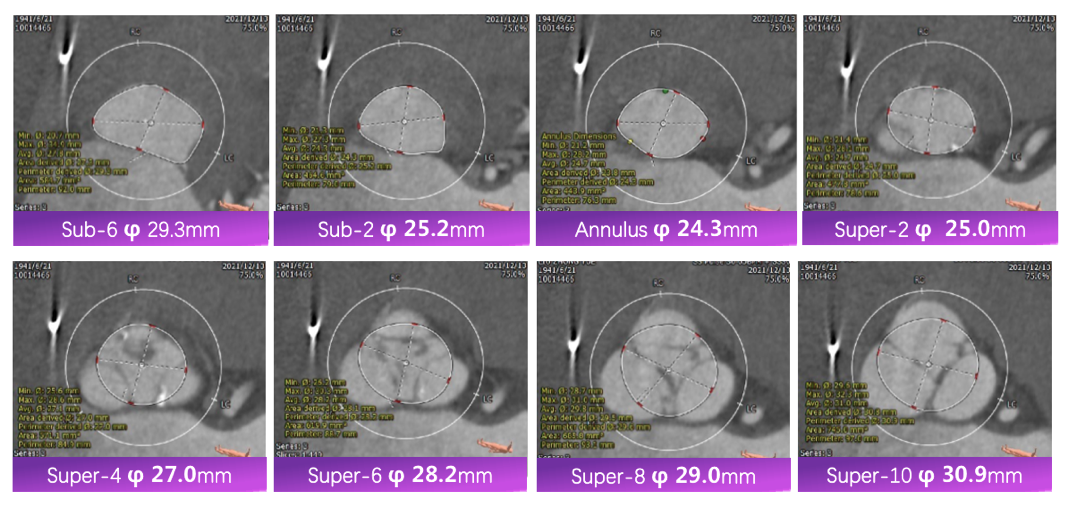

CT评估

3. 在J型导丝指引下,使用6F pigtail造影导管进入左心室,测得主动脉瓣跨瓣压差15mmHg, 升主动脉血压180/40mmHg, 左心室压力165/5mmHg, 交换为特硬导丝Lunderquist至左心室,结合术前冠脉CT和心脏超声测量的瓣环直径大小,选择VitaFlow Liberty™30可回收瓣膜系统送至主动脉瓣环处,在Pigtail导管定位,主动脉根部造影协助指导下,精准定位,以180次/分快速起搏,逐步释放瓣膜,支架释放后退出导管输送系统,猪尾导管行主动脉根部造影示:人工瓣膜深度4mm, 冠状动脉开口未受影响,食道超声提示无主动脉瓣反流。